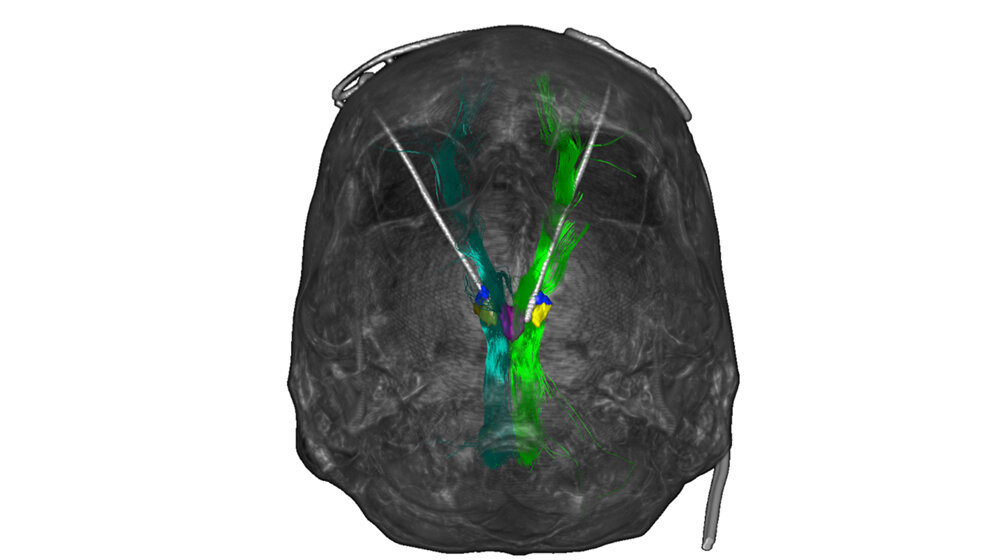

Die acht Probanden litten zwischen drei und elf Jahre durchgehend an einer schwersten Depression, bei der weder medikamentöse oder psychotherapeutische Behandlungen noch Stimulationsverfahren wie die Elektrokrampftherapie Besserung brachten. Die Ärzte implantierten hauchdünne Elektroden und stimulierten einen Hirnbereich, der an der Wahrnehmung von Freude beteiligt und damit auch für Motivation und Lebensqualität von Bedeutung ist. Die Wirkung der Therapie bewerteten die Ärzte monatlich mit Hilfe der etablierten Montgomery-Asberg Rating Scale (MARDS). Bereits im ersten Monat fiel der MARDS-Wert im Durchschnitt von 30 Punkten auf 12 Punkte und sank bis zum Ende der Studie sogar noch weiter leicht ab. Den MARDS-Wert von 10 Punkten, ab dem eine Depression diagnostiziert wird, unterschritten vier Personen.

Manche Patienten litten kurzzeitig unter verschwommenem Sehen oder unter Doppelbildern. „Die Nebeneffekte konnten wir durch eine verminderte Stimulationsstärke beheben, ohne dass der antidepressive Effekt der Therapie nachgelassen hätte“, sagt Prof. Dr. Volker A. Coenen, Leiter der Abteilung Stereotaktische und Funktionelle Neurochirurgie an der Klinik für Neurochirurgie des Universitätsklinikums Freiburg. Bei keinem Patienten waren Persönlichkeitsveränderungen, Denkstörungen oder andere Nebenwirkungen zu beobachten.